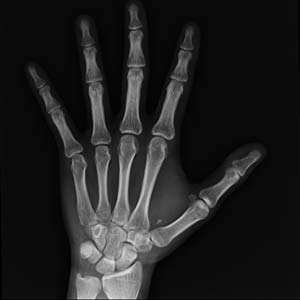

![]() ![]() 중국과학원 분자세포과학탁월혁신센터(생화학세포생물학연구소) 연구팀은 VGLL4가 TEADs 매개체의 RUNX2 전사 억제를 깨뜨려 골모세포 분화 및 골격의 발달을 촉진함을 입증했다. 해당 성과는 "VGLL4 promotes osteoblast differentiation by antagonizing TEADs-inhibited Runx2 transcription"라는 제목으로 "Science Advances"에 온라인으로 게재되었다. Hippo 신호 통로의 새로운 구성원인 VGLL4는 전사보조인자 YAP와 경쟁하여 전사인자 TEAD에 결합함으로써 YAP-TEADs 전사 복합체의 활성을 억제하고 성장 발달 조절을 달성할 수 있다. 그러나 VGLL4의 골격 발달과 골격 향상성에서의 정확한 기능은 밝혀지지 않았다. 연구팀은 골모세포의 분화 장애로 인해 중간엽 줄기세포와 골모세포 중 VGLL4의 녹아웃이 골다공증과 전방 두개골 이형성증과 같은 표현형을 나타냄을 발견했다. 메커니즘 측면에서, TEAD 전사인자는 YAP에 의존하지 않는 방식으로 골모세포의 분화를 심하게 억제한다. TEAD는 RUNX2와 상호 작용하여 RUNX2 전사 활성을 억제한다. 또한 VGLL4는 RUNX2와 직접 경쟁하여 2개의 TDU 도메인을 통해 TEAD에 결합함으로써 TEAD의 전사 억제를 감소시킨다. 해당 연구는 VGLL4의 골모세포 분화 및 골격 발달 조절에서의 중요한 작용을 규명하였다. 아울러 TEAD의 RUNX2 전사 활성 조절은 두개골 이형성증과 골다공증 치료에 새로운 방향을 제시했다. 정보출처 : http://www.most.gov.cn/gnwkjdt/202011/t20201127_159827.htm |